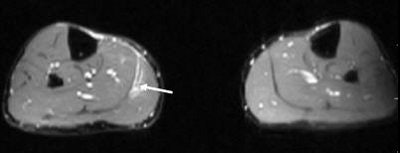

![]() |

A 35-year-old male with a partial rupture of the medial head of the gastrocnemius at the musculotendinous junction. Top, the longitudinal US image shows the medial head of the gastrocnemius muscle with partial discontinuity of the muscle fibers (double arrows). A small hypoechoic fluid collection (single arrow) is noted. G = gastrocnemius muscle, S = soleus muscle. Below, the longitudinal US image one week later shows a hyperechoic fluid collection (arrows). This fluid can be considered as most likely representing flesh blood.